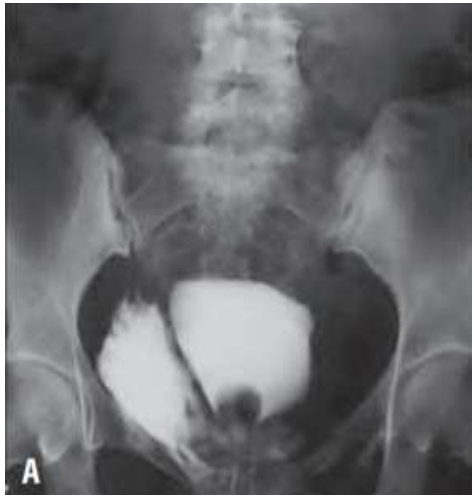

Mariana, 45 anos, é trazida pelo SAMU, vítima de acidente carro-moto. Suspeita de fratura de bacia. Refere dor abdominal intensa. Na admissão, realizado analgesia, coletados exames laboratoriais, avaliação da equipe da Ortopedia e realizado sondagem vesical para controle do débito urinário, com hematúria franca. Na hipótese de trauma de bexiga, foi solicitada pelo médico plantonista, uma cistografia retrógrada (imagem abaixo):

De acordo com o quadro clínico descrito e o exame de imagem solicitado, assinale a alternativa correta: